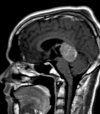

Q

35 anos, Masculino

A

Craniofaringioma adamantinomatoso

Craniofaringioma adamantinomatoso Crianças Lesão suprasselar com componente sólido e cístico; lobulado; calcificação anelar ou nodular presente em quase TODOS os craniofaringeomas pediátricos; Componente cístico proeminente e componente sólido pequeno, mas com realce.